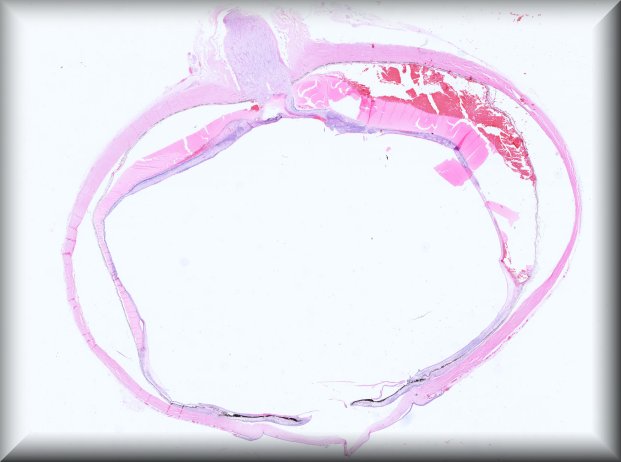

Martina Herwig-Carl (Bonn): 57 year old woman with a blind painful eye and history of intrvitreal bevacizumab injections, tumour biopsy and brachytherapy for uveeal melanoma followed by several proceedures for high intraocular pressure resulting finally in enucleation. |